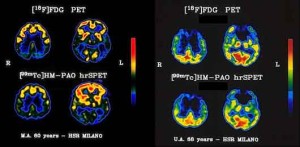

Individuati due nuovi geni, BIN1 e CNTN5, “sospettati” di essere coinvolti nello sviluppo dell’Alzheimer a esordio tardivo (dopo i 60 anni): la scoperta è stata effettuata da un team del Massachusetts General Hospital di Boston e pubblicata su Archives of Neurology. I due geni si aggiungono ad altri 4 geni già noti, uno dei quali conosciuto come uno dei principali “autori del reato” (apoE4) e altri tre considerati “fortemente indiziati” (CLU, CRI, PICALM). Gli esperti, guidati da Alessandro Biffi e Christopher Anderson, hanno usato la risonanza magnetica per studiare i cambiamenti nelle strutture cerebrali – come le dimensioni del ippocampo e dell’amigdala – in 700 soggetti sani e malati di Alzheimer, in combinazione con l’utilizzo di programmi al computer per ordinare le sequenze genetiche dei volontari per capire se c’erano, e quali fossero, le mutazioni legate alla forma di demenza più comune che colpisce circa 26 milioni di persone al mondo.

Lo studio, che ha indagato in particolare la forma di Alzheimer a esordio tardivo, ha confermato il ruolo dei 4 geni fortemente collegati alla patologia e ne ha individuati altri due dalla relazione “sospetta” con la patologia: “Questi risultati possono contribuire – spiegano i ricercatori – a dare la priorità a futuri studi genetici”.

Biffi e colleghi sospettano, in particolare, che i geni possano spiegare il 60-80% delle cause di insorgenza tardiva dell’Alzheimer: mentre diversi studi, spiegano i ricercatori, hanno ormai da tempo individuato che la causa dell’insorgenza precoce dell’Alzheimer (la forma rara che colpisce soggetti sotto i 60 anni) è genetica, sono invece ancora poche le ricerche che collegano le cause genetiche all’esordio tardivo della patologia. (ASCA)